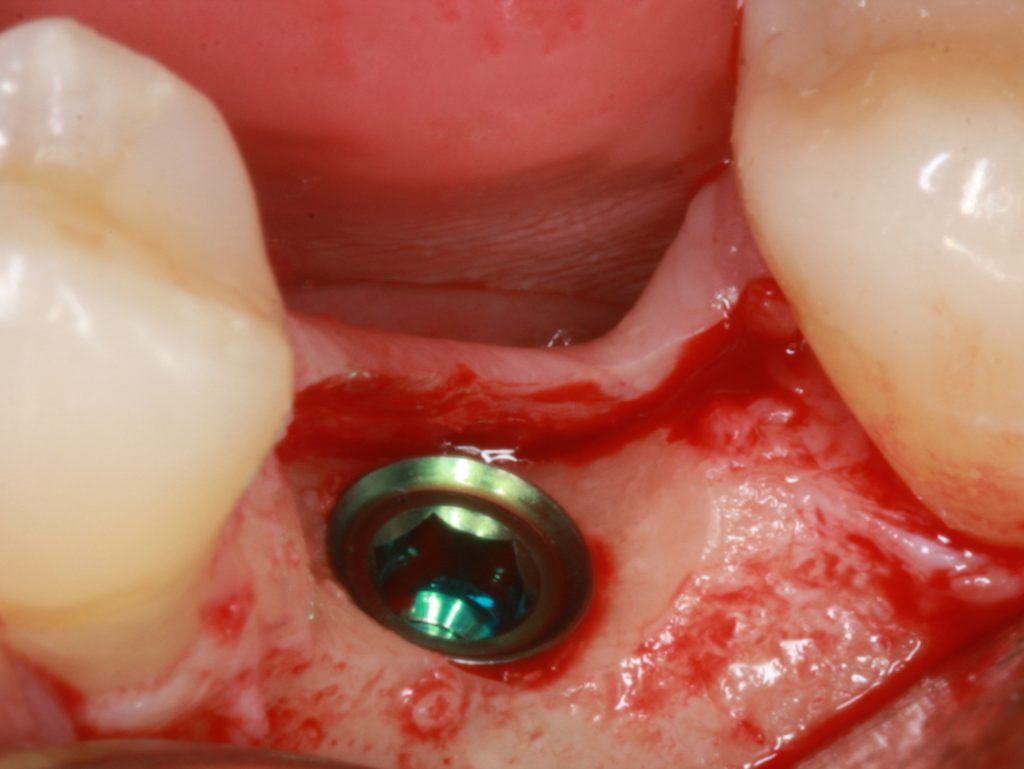

image

Thin vertical soft tissue thickness must be measured before implant placement

Furthermore, it was clearly shown that even implants with platform switching modification couldn’t maintain bone if, at the time of implant placement, vertical soft tissues were thin.